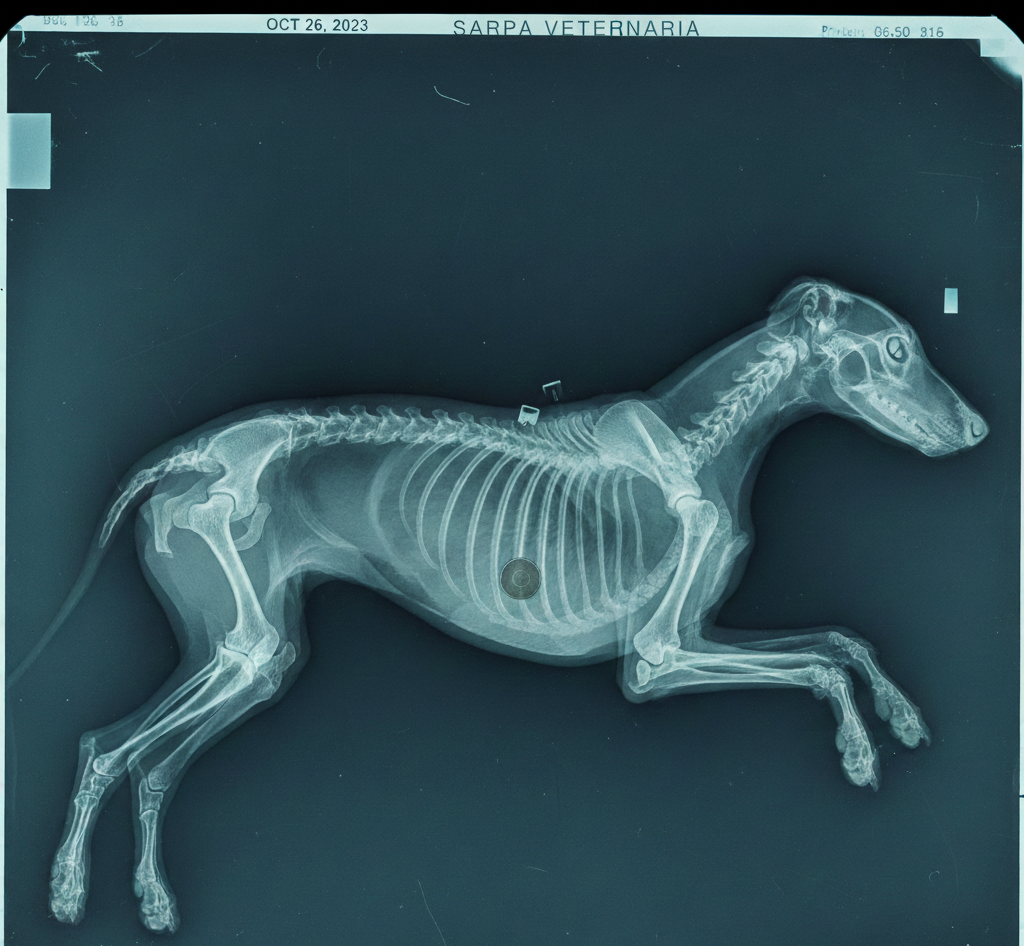

Radiografia perro y ecografía veterinaria

¿Tu perro muestra dolor, cojea o notas cambios que no sabes explicar? Antes de tomar una decisión, necesitas una imagen clara. La radiografia perro y la ecografía veterinaria son pruebas clave para detectar el problema con rapidez y seguridad. En esta categoría de SARPA VETERINARIA encontrarás el equipamiento necesario para ofrecer un diagnóstico profesional y fiable en tu clínica.

La radiografia perro es ideal cuando existen:

- Sospechas de fracturas o luxaciones.

- Problemas articulares o displasia.

- Dificultades respiratorias.

- Ingestión de cuerpos extraños.

- Dolores abdominales persistentes.

Permite visualizar huesos, pulmones y estructuras internas con gran precisión.